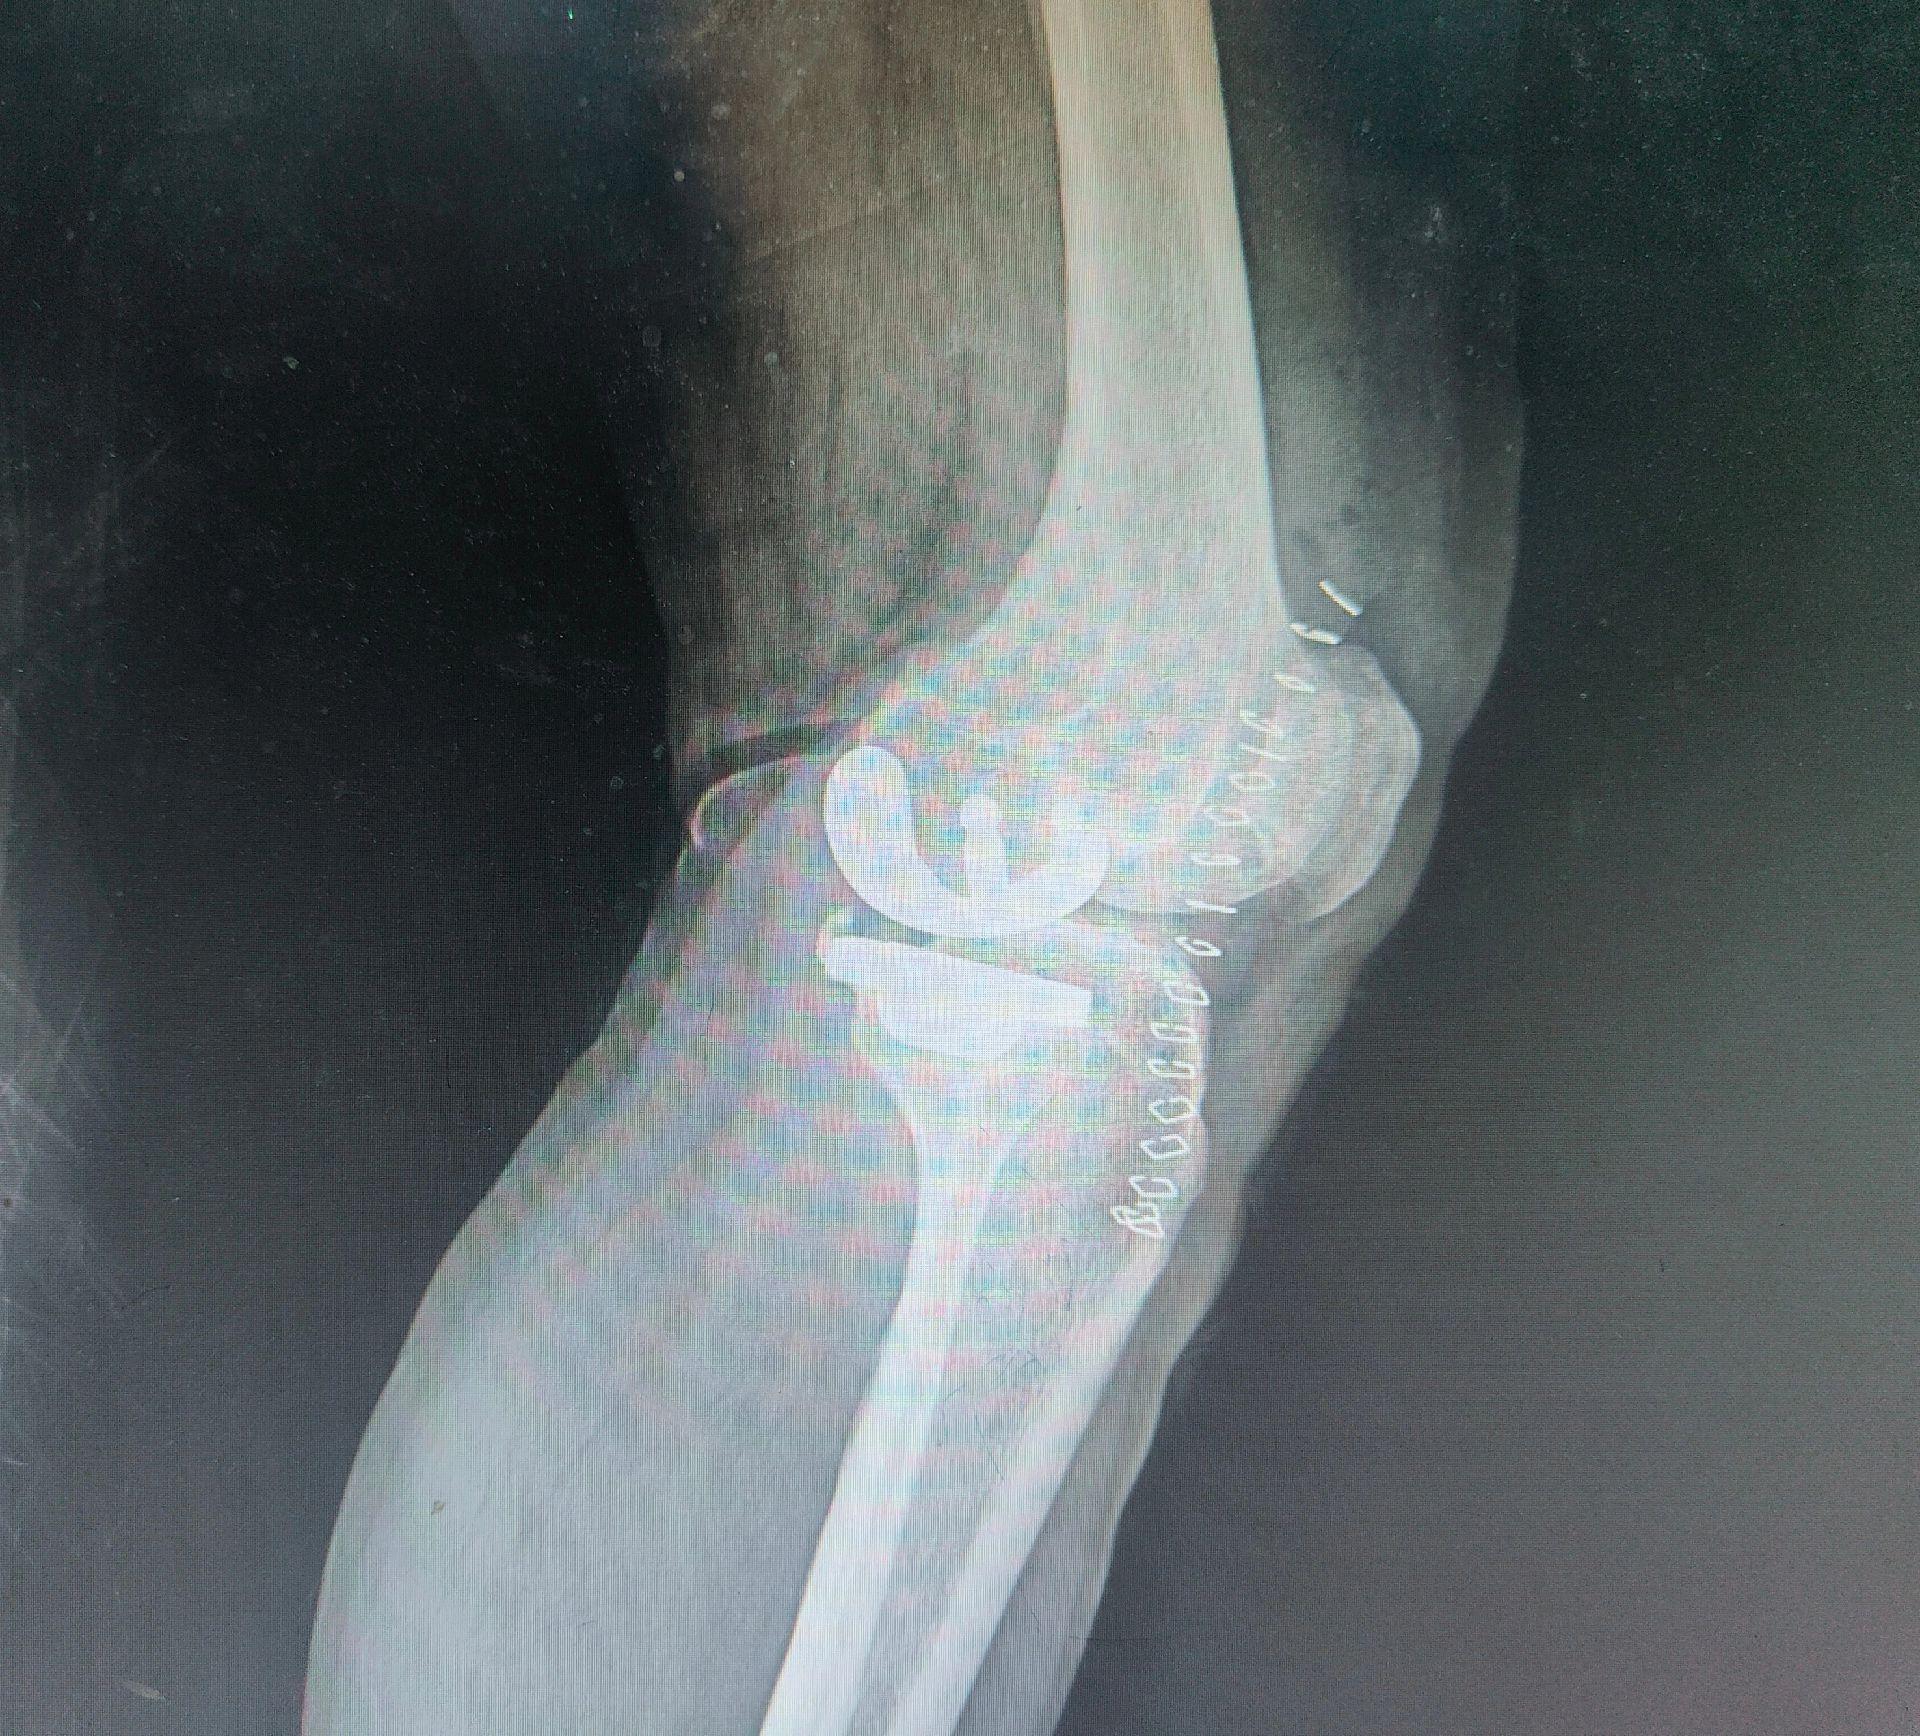

单髁置换术。(看图猜假体)每款假体都有自己的优点,不要单纯追求国产或进口,也不要单纯追求活动平台或固定平台,适合自己才是最好的。愿每一位病人都能快速顺利康复🌹